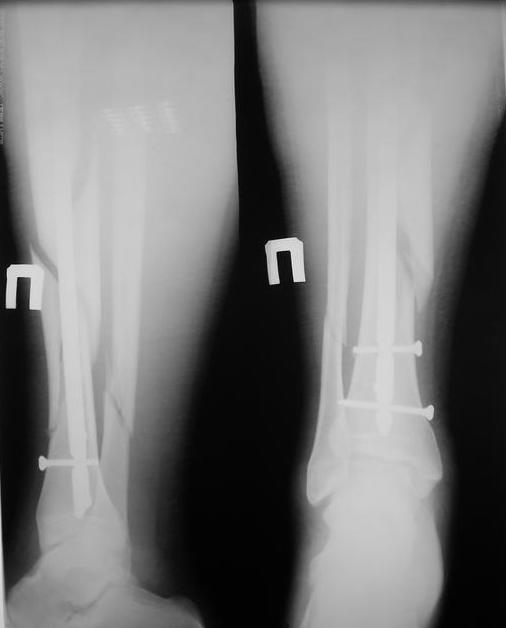

Уважаемые коллеги травматологи подскажите как нам быть и что делать. Думали всем

отделением.Несрощение оскольчатого перелома костей голени после интрамедуллярного

блокируемого синтеза.

У нас был молодой пациент М.(26лет), травма 25 января 2009г, катался на лыжах и получил

травму. Поступил к нам в отделение в экстренном порядке. При обследованиии выявлен закрытый

винтоообразный оскольчатый перелом правой большеберцовой кости и косой перелом

малоберцовой кости на границе средней и нижней трети. Выполнен интрамедуллярный

блокируемый синтез большеберцовой кости, оси и длина конечности восстановлена. После

операции пациент ходил с полной нагрузкой. Через 3 месяца на контрольных рентгенограммах

сращения нет, динамизации не выполняли, так как оскольчатый перелом.(снимки в динамике

прилагаются). Посоветуйте, что в данном случае делать наиболее целесообразно?